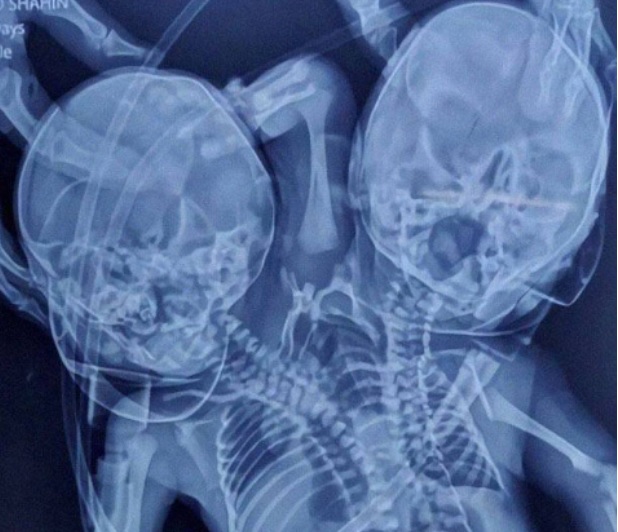

Nace bebé siamés con dos cabezas, dos corazones y tres manos

Tras meses de embarazo y esperar el nacimiento de sus gemelos, la mujer Shaheen Khan, dio a luz a un bebé siamés con dos cabezas, dos corazones y tres manos en el estado de Madhya Pradesh, al centro de la India.

El nacimiento del infante es conocido en la pediatría como parapagus dicefálico, que es cuando dos fetos que comparten vientre están unidos por un solo torso, lo cual complica la vida del recién nacido.